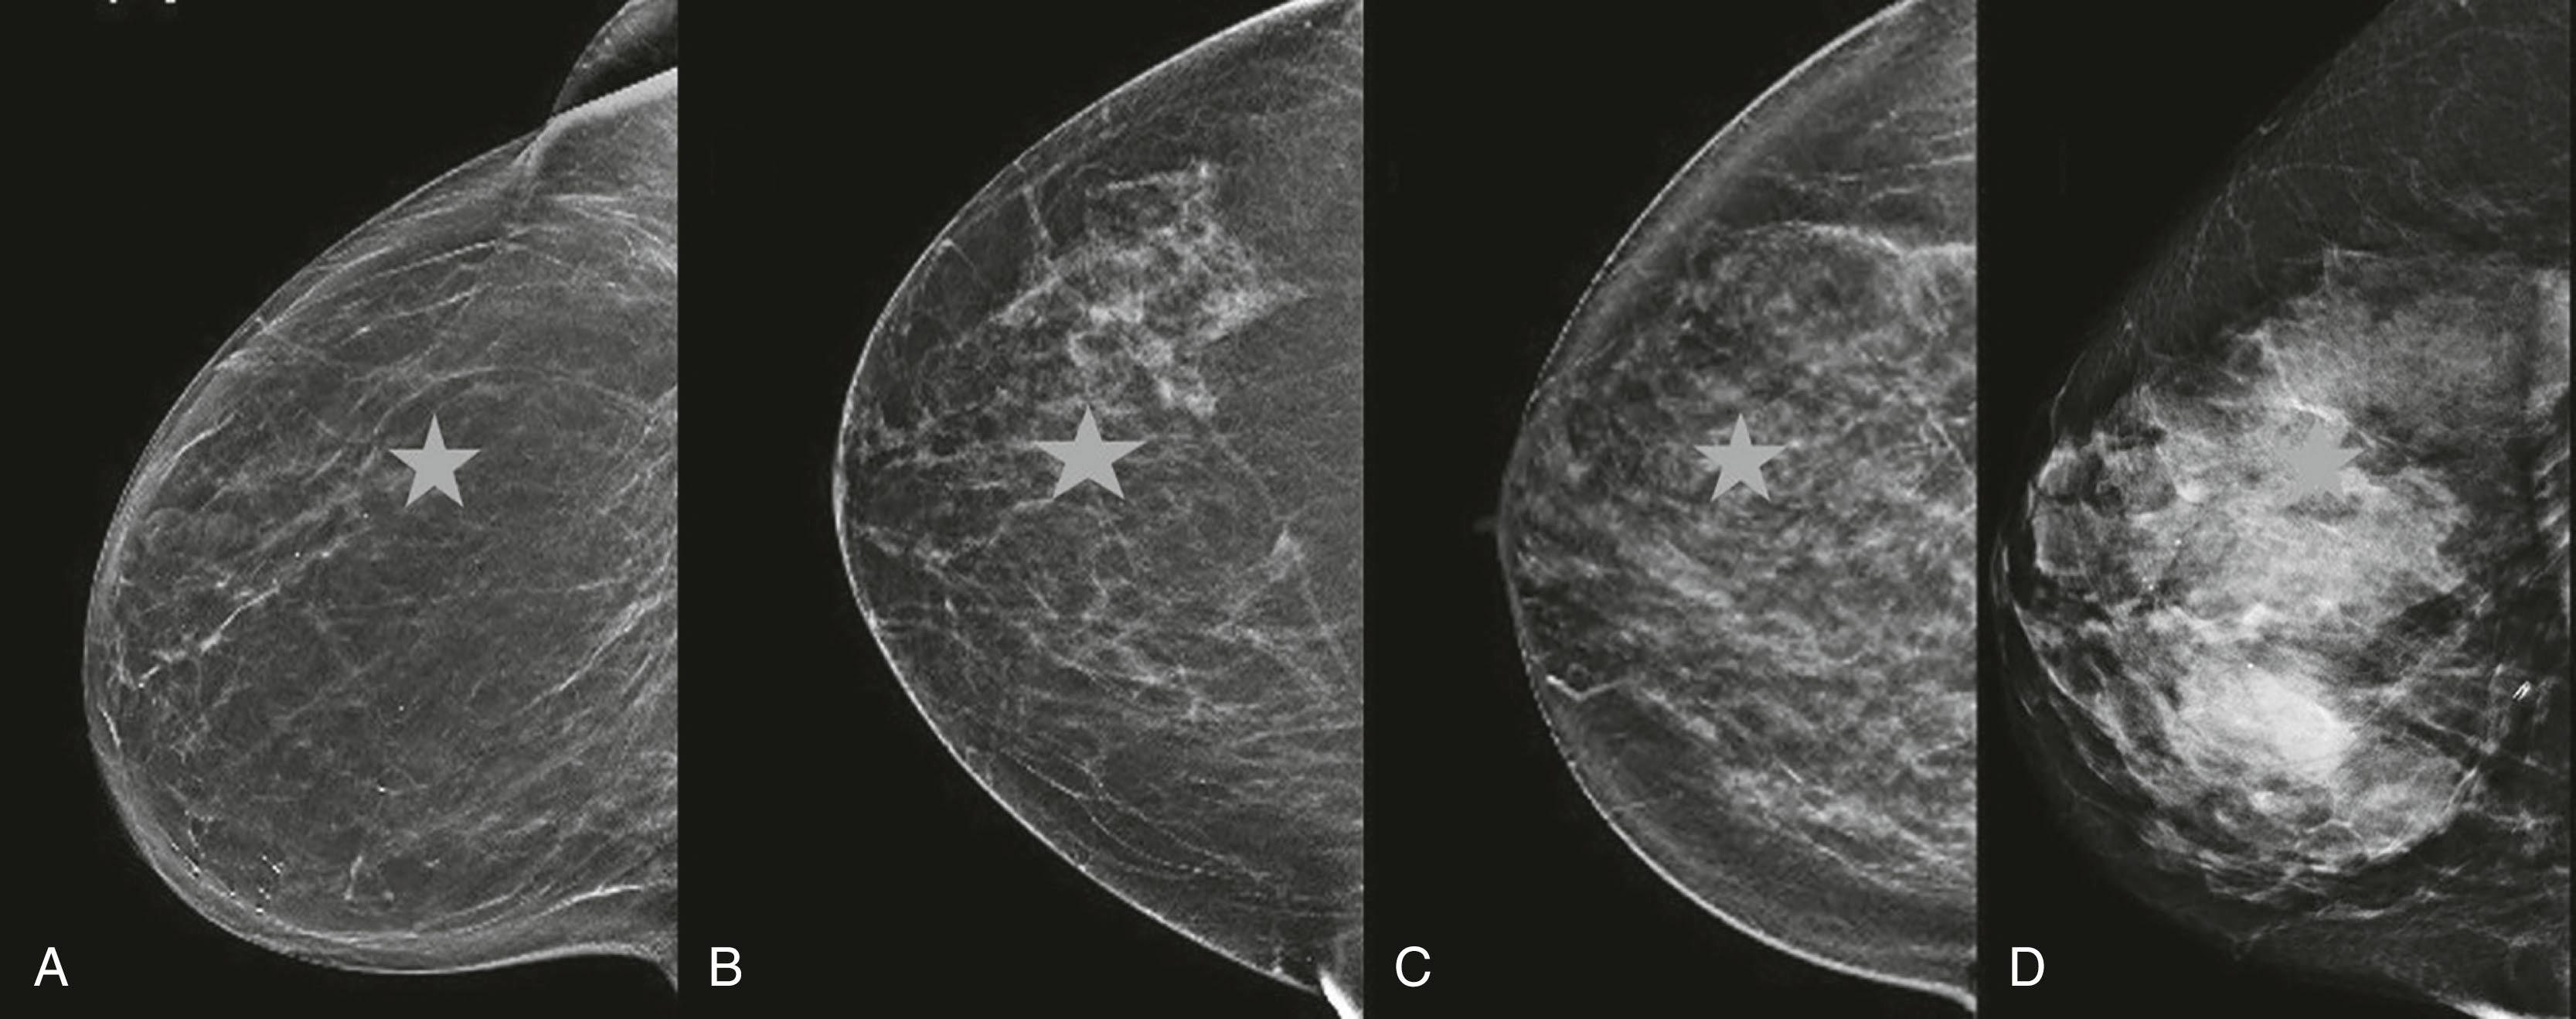

Screening Mammography Report

The report starts with an overall assessment of breast density that refers to the amount of fibroglandular tissue as compared to the amount of fatty tissue within the breast. High mammographic density both reduces diagnostic accuracy of screening mammography due to tumors masked by overlaying breast tissue and is an independent risk factor for breast cancer. Young age, pregnancy, lactation, and hormonal treatment are associated with increased breast density. There are four descriptors for breast density in the BI-RADS lexicon, with progressively decreased mammographic sensitivity for cancer detection: (1) fatty, (2) scattered areas of fibroglandular density, (3) heterogeneously dense, which may obscure small masses, and (4) extremely dense, which lowers the sensitivity of mammography ( Fig. 12.5 ).

Fig. 12.5, Fibroglandular tissue density categories: (A) fatty, (B) scattered areas of fibroglandular density, (C) heterogeneously dense, and (D) extremely dense. A star shape simulating a suspicious lesion is almost entirely obscured in dense breast.